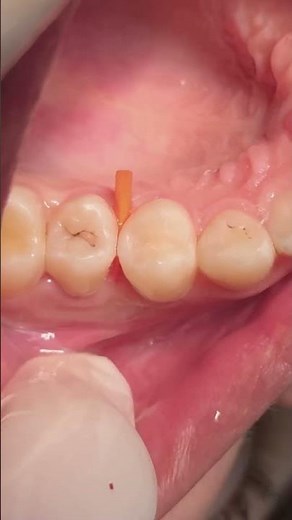

- Class 2

Filling - Class 1

Restoration - Class II

Composite Restoration - Molar